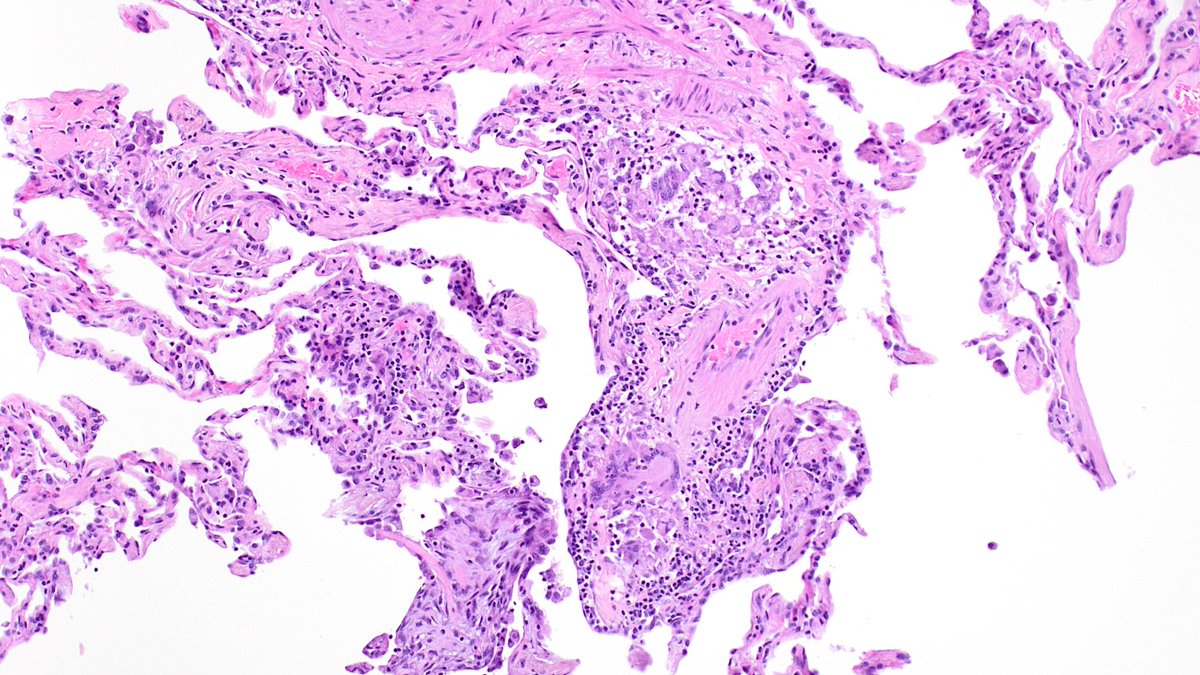

Diagnosing granulomatosis with polyangiitis on small biopsies (especially if not considering it) is very challenging. ANCA serologies, negative cultures, and pathologic suspicion were crucial in this case. Not everything is cancer at a cancer center. #lungpath #pathology #moffitt

What to do with ill-formed interstitial granulomas on lung resections for malignancy? When are interstitial mononuclear inflammatory cells too numerous? (Same case, away from tumor) #moffitt #moffittpath #lungpath #moffittpathology